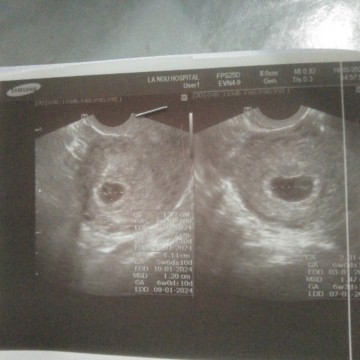

อายุครรภ์ 6 สัปดาห์ 5 วันพบแต่ถุงตั้งครรภ์กับถุงไข่แดง แต่ไม่พบตัวเด็ก แบบนี้ ปกติไหมค่ะ#ขอบคุณล่วงหน้านะคะ

คุณหมอนัดอีกทีตอน 10W ค่ะ เดี่ยวมาลุ้นกันค่ะว่าจะเจอน้องไหม